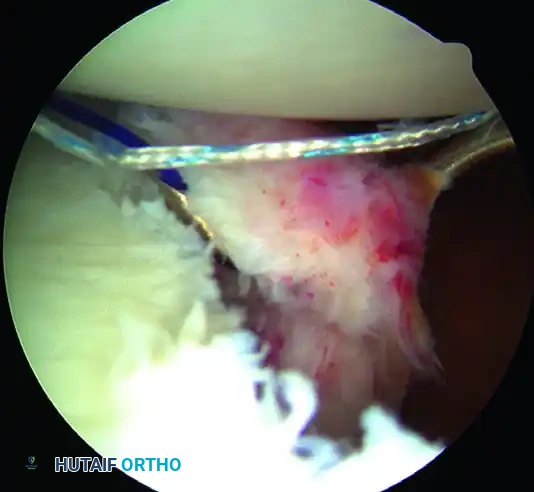

1. Capsulolabral Mobilization and Glenoid Preparation

The most common cause of failure in Bankart repair is inadequate mobilization of the capsulolabral complex.

While visualizing from the anterosuperior portal, use an arthroscopic elevator or radiofrequency wand to meticulously free the capsule down to the 6-o’clock position. You must release the tissue until the underlying red muscle belly of the subscapularis is clearly visible. This complete release is mandatory to allow the inferior capsule to be shifted superiorly without tension.

💡 CLINICAL PEARL: The Biological Bed

Soft tissue healing requires a robust vascular response. Use an arthroscopic rasp or motorized burr to abrade the anterior glenoid neck down to bleeding cancellous bone. Do not over-resect the bone, as preserving the cortical edge is necessary for secure anchor purchase.

A, Abrasion of glenoid neck and capsular release to allow advancement of capsulolabral complex superiorly and laterally to restore anatomy and physiological tension.